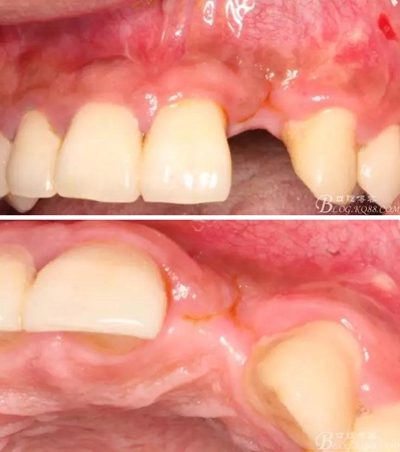

4個月后,唇側(cè)豐滿度尚可,與鄰牙之間齦乳頭完整。

保留齦乳頭翻小瓣。

戴入永久修復(fù)體當(dāng)天口內(nèi)照,雖有小瑕疵,但患者很滿意。